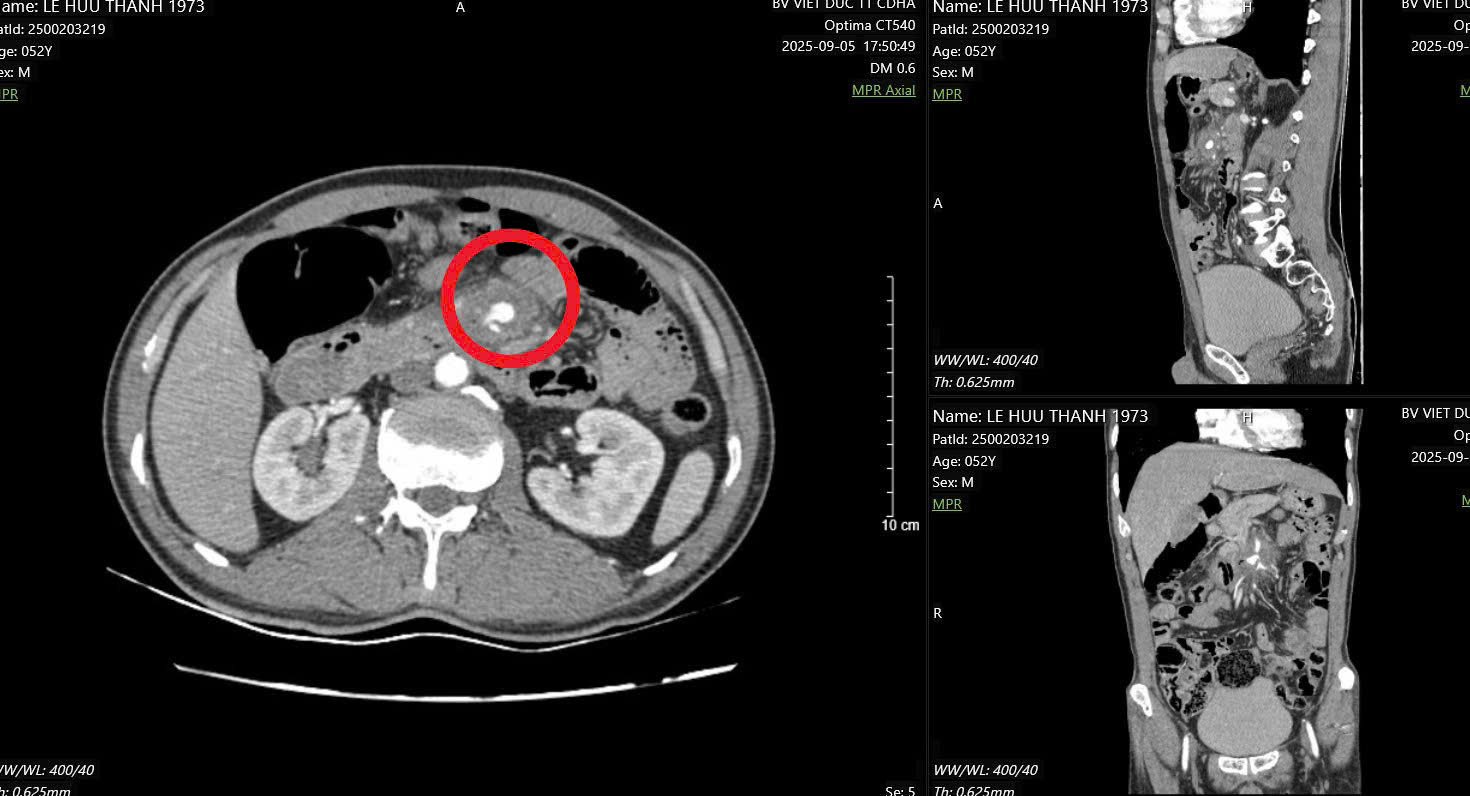

Hình ảnh đoạn D3 tá tràng tổn thương, cạnh động mạch mạc treo tràng trên

Nguy hiểm hơn, đầu tăm tiếp tục đâm vào một trong những mạch máu lớn nhất trong ổ bụng – động mạch mạc treo tràng trên, là nơi đưa máu nuôi phần lớn ruột non. Tổn thương này đã khiến thành mạch máu bị phồng lên giả tạo (gọi là “giả phình mạch”), nếu không được phát hiện và xử trí kịp thời có thể gây vỡ mạch, chảy máu ồ ạt trong ổ bụng, đe dọa tính mạng.